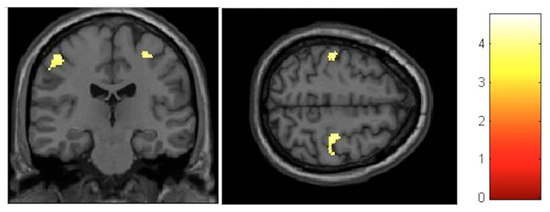

| Effect | Brain Region | Left Hemisphere MNI Coordinates (Cluster Size in Voxels) | T | d | Right Hemisphere MNI Coordinates (Cluster Size in Voxels) | T | d |

|---|---|---|---|---|---|---|---|

| Increment | Sensory-motor | −8, −32, 60 (314) | 5.17 | 0.39 | 11, −29, 60 (1087) | 6.09 | 0.41 |

| Decrement | Hippocampus | 27, −30, −6 (133) 23, −2, −17 (119) | 4.06 4.74 | 0.37 0.38 | |||

| Decrement | Insula | −33, −12, 18 (586) | 5.57 | 0.40 | 33, −17, 17 (797) | 6.17 | 0.41 |

| Decrement | Putamen | −26, 8, 6 (631) | 4.72 | 0.38 | 21, 11, 2 (134) | 4.22 | 0.38 |

| Decrement | Cerebellum | −11, −45, −23 (245) | 3.84 | 0.36 | 11, −65, −23 (224) | 3.99 | 0.37 |